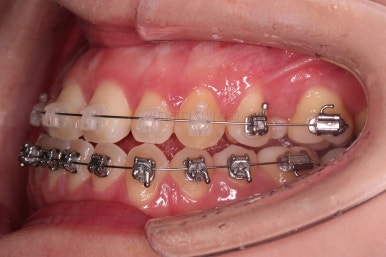

이번 환자분이 선택하신 장치는 눈에 많이 띄는 윗니는 자가결찰 세라믹(데이몬 클리어, Damon clear), 아랫니는 자가결찰 메탈(엠파워 메탈, Empower metal)을 사용했어요.

장치 부착 후의 모습은 참고해 주시고요.

폭이 맞아지고 치아 배열을 조금 시행하니 송곳니 부분에서의 반대교합이 금새 개선된 것을 알 수 있으실거에요.

이렇게 측방으로의 반대교합만 개선이 되어도 턱관절에서의 불편감은 많이 줄어들게 됩니다.